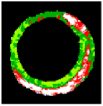

Figure 7 depicts the effectiveness of the KMPSO-mED model by segmenting the overlapping tissues in VH-IVUS images.

Figure 7.

Segmentation by KMPSO-mED: (a) overlapped tissue, and (b) segmented area.